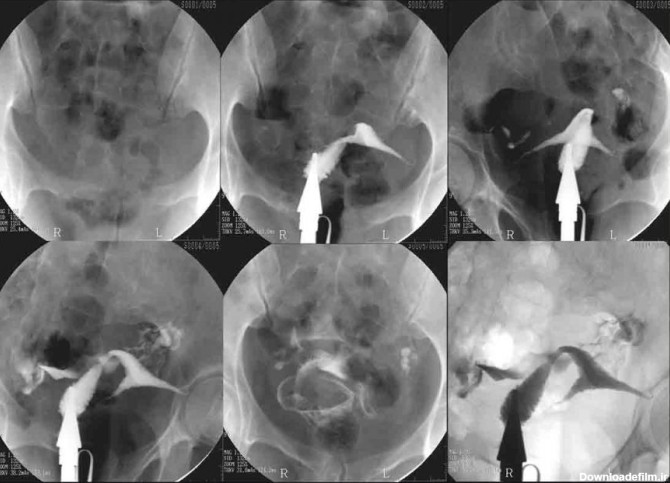

عکس رنگی رحم یا هیستروسالپینگوگرافی به معنای استفاده از اشعه ایکس برای مشاهده رحم و لولههای فالوپ است.

عکس رنگی رحم بدون درد؛ هیستروسالپنگوگرافی برای مشاهده داخل رحم و لوله های فالوپ استفاده می شود. می تواند نشان دهد که داخل رحم اندازه و شکل طبیعی دارد یا خیر.